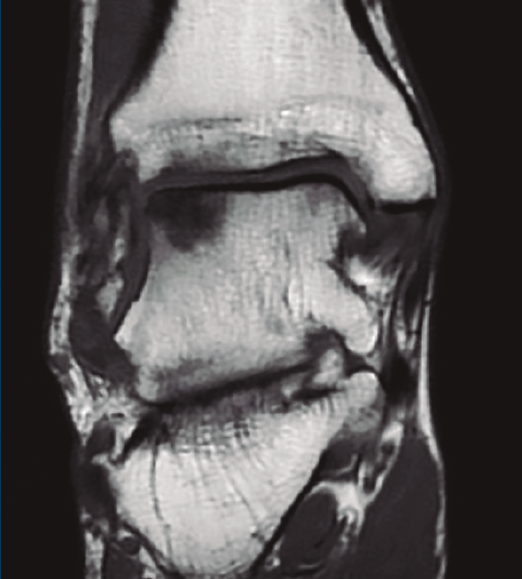

Un paciente presentaba lesiones de cartílago considerables a nivel de la cúpula astragalina secundarias a la afección sinovial que se trataron con legrado y perforaciones (Figuras 2 y 3).

Figura 2. Lesión osteocondral a nivel de la cúpula astragalina en paciente afecto de tumor difuso de células gigantes de tobillo.